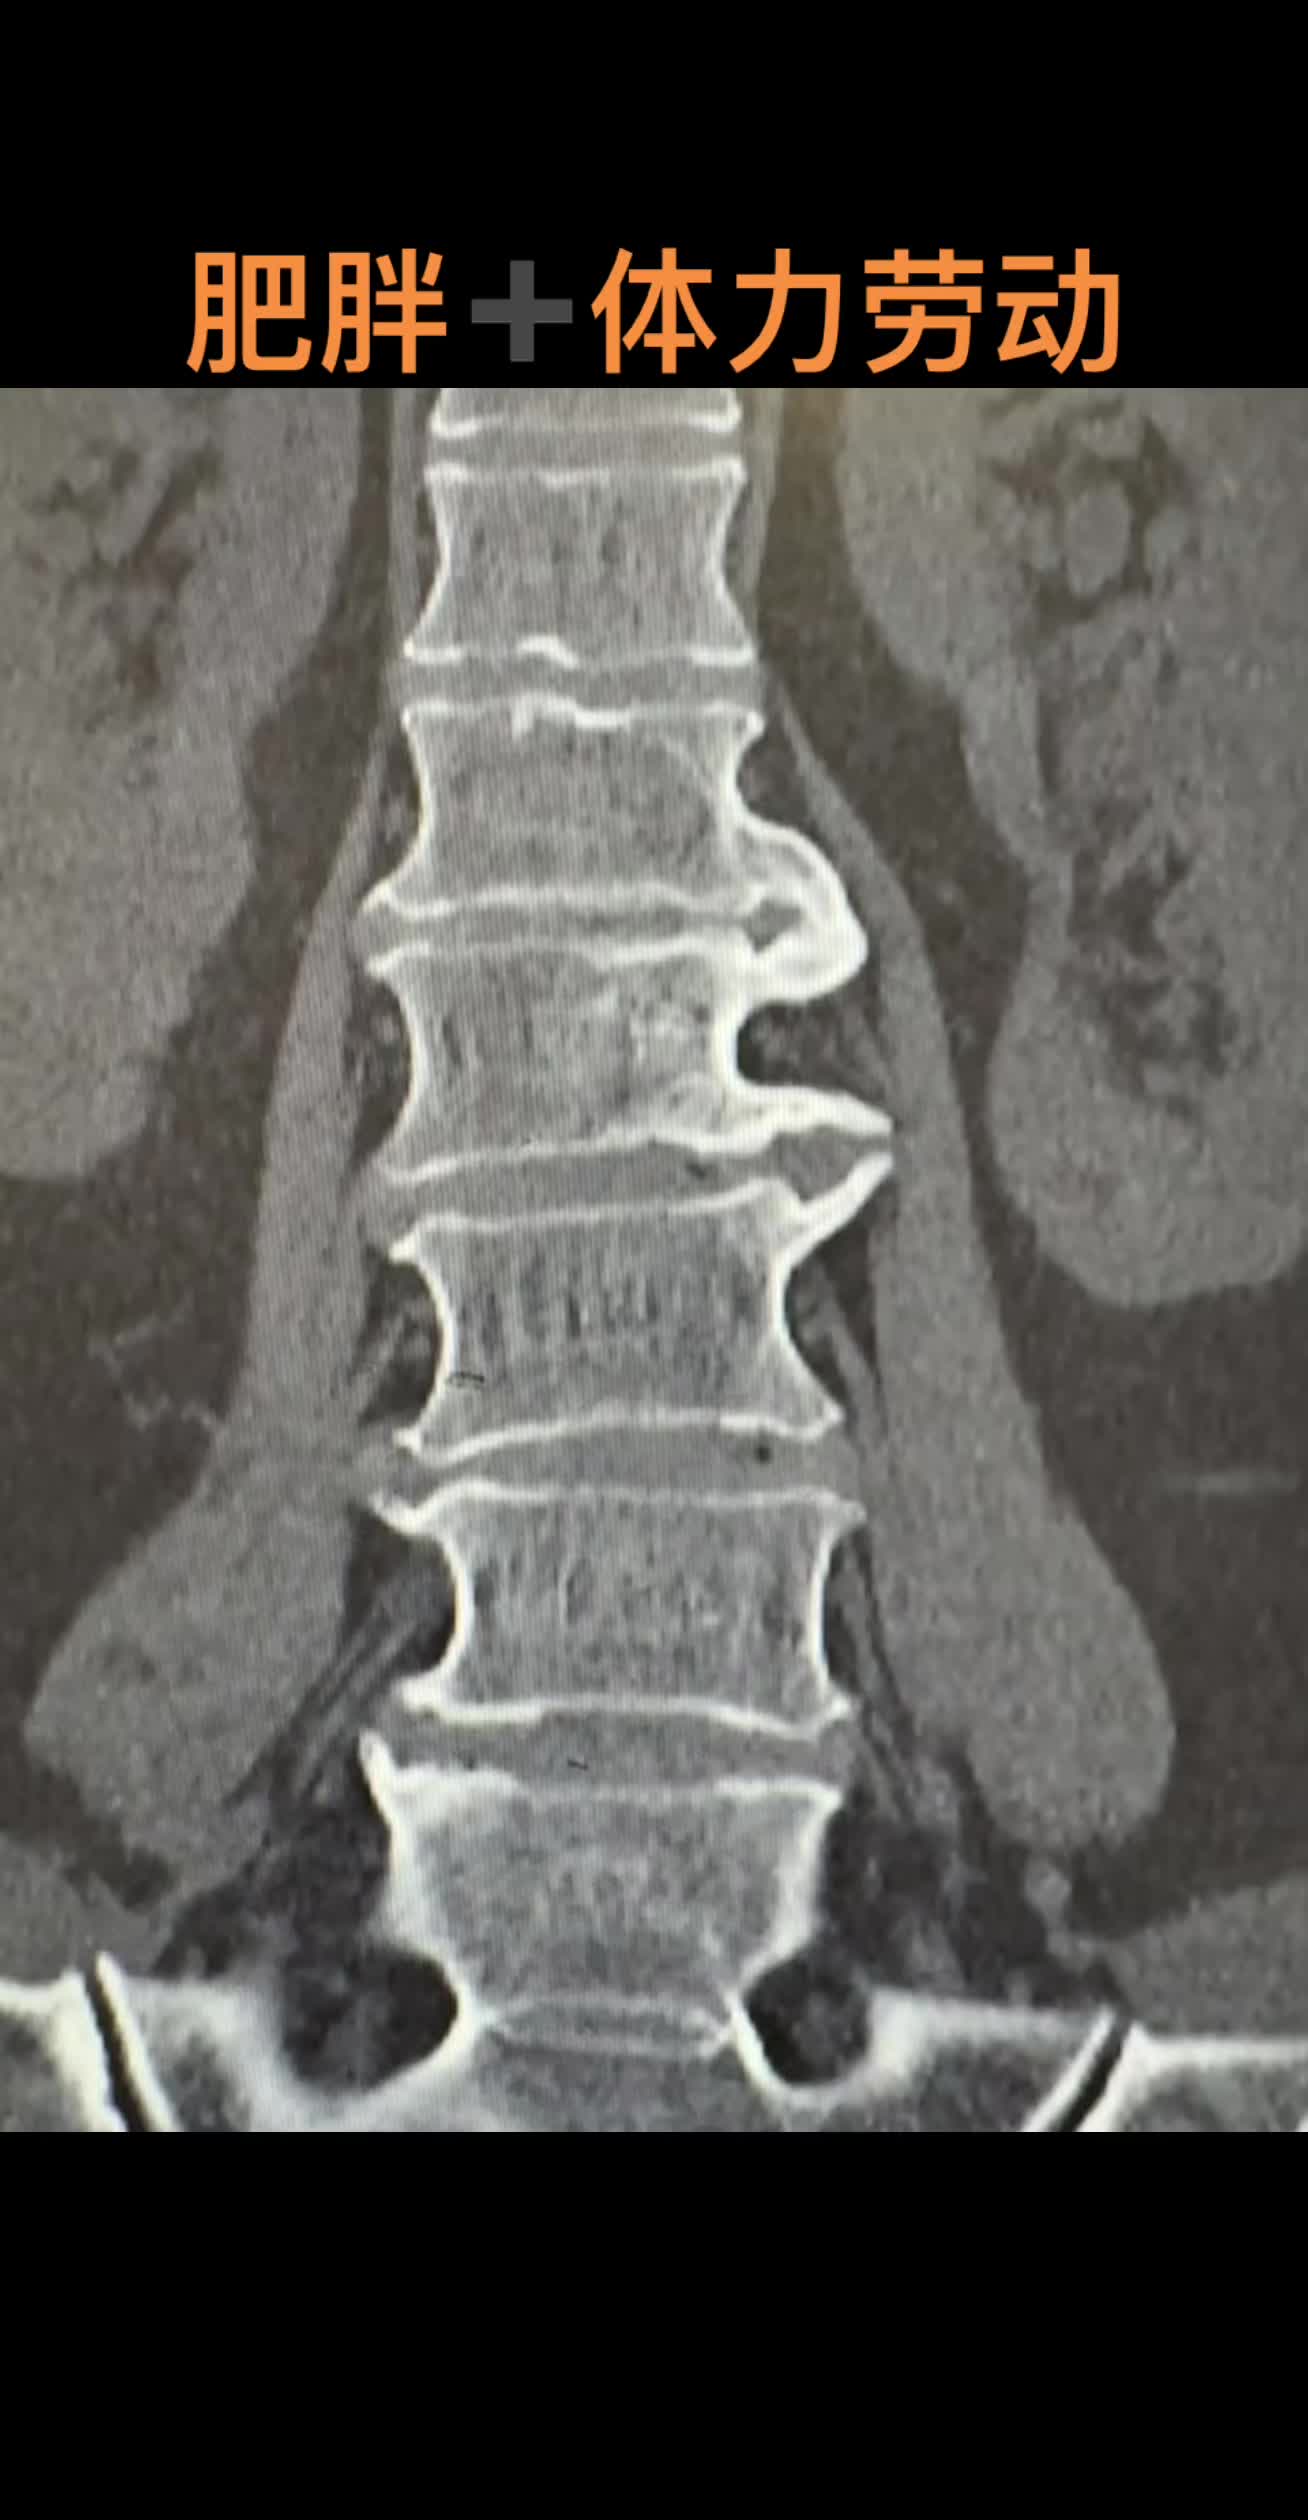

腰痛 骨质增生教科书般的退行性腰椎病

腰痛 腰椎退行性变骨质增生腰椎滑脱 教科书般的退行性腰椎病